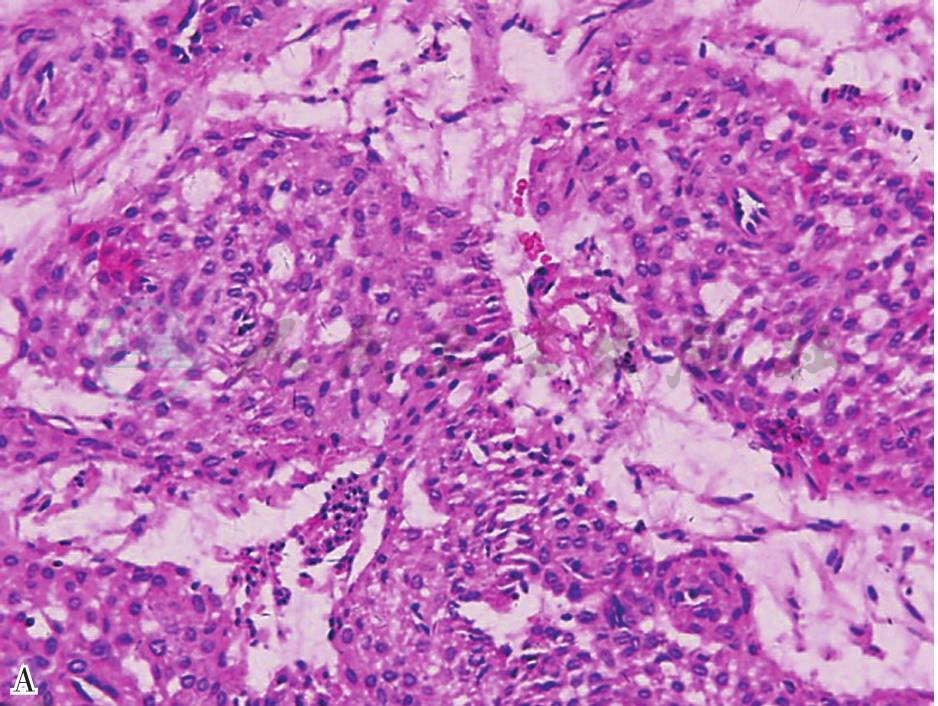

组织病理见许多血管腔衬以单层扁平内皮细胞,内皮细胞周围为数层或多层球细胞,球细胞为平滑肌细胞Vimentin染色阳性(图1)。

图1 肿瘤细胞为圆形细胞,细胞膜界限清楚,围绕于血管周围(HE,×40)